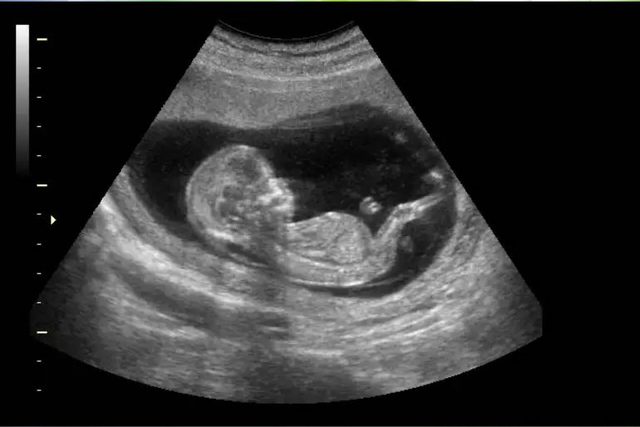

Se inventó el ultrasonido, hasta el día de hoy se utiliza para el diagnóstico de embarazos u otras patologías en los órganos

El uso del ultrasonido de alta frecuencia en problemas marítimos se inició en la primera guerra mundial y las investigaciones, entre 1948 y 1958, para la aplicación de esta técnica al diagnóstico fue un trabajo en conjunto de personal y equipo militar, industrial y médico; sin embargo, no fue hasta finales de los 70 que se lograron los equipos a tiempo real tal como los conocemos actualmente.